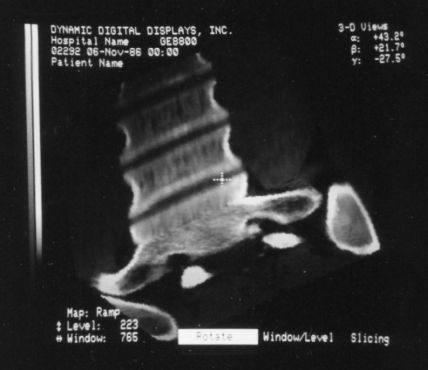

These photos of the Voxelscope II screen are typical of the types of rendering provided by the system.

Voxelscope II Screen Shots. Combination of 3-D Shaded Surface, Multiplanar Reformatting, and Segmentation